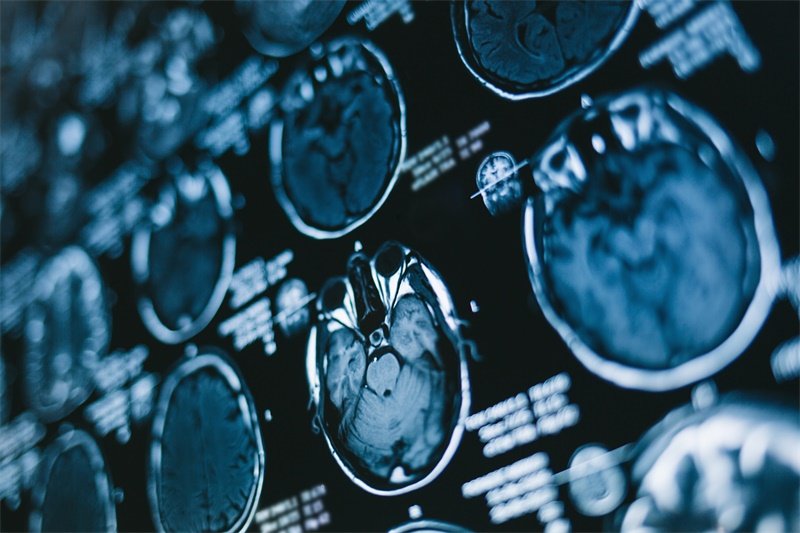

由于以上症状与其他疾病相似,确诊蝶窦癌需要进行专业的影像学检查,如MRI或CT等,以清晰显示病变情况。

- 影像学检查:利用CT或MRI技术确认占位的形态、大小及位置